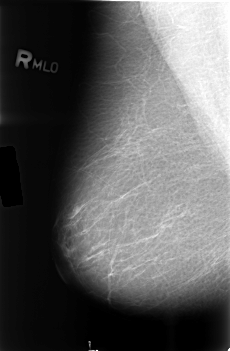

B_3433_1.RIGHT_MLO

RIGHT_MLO LINES 4560 PIXELS_PER_LINE 2984 BITS_PER_PIXEL 12 RESOLUTION 50 NON_OVERLAY